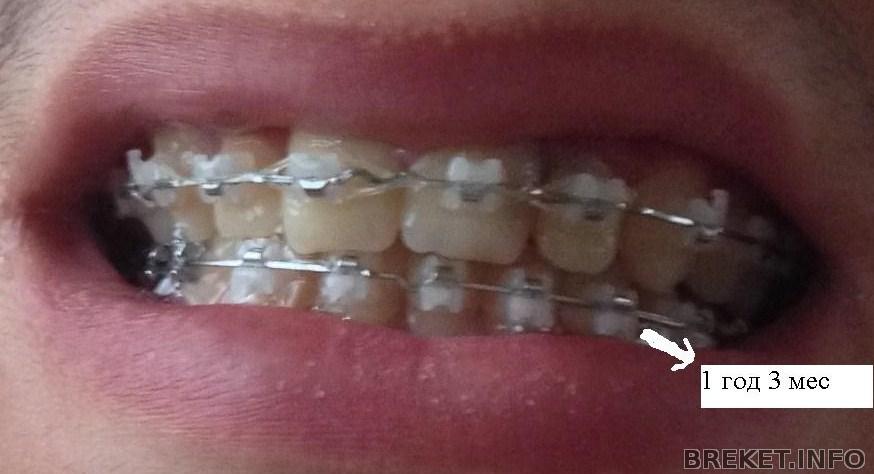

Такой наклон моих резцов (примерно)

И ретейнер на ВЧ клеить некуда

Но делать новые "портфолио" было волнительно

позировала, как могла